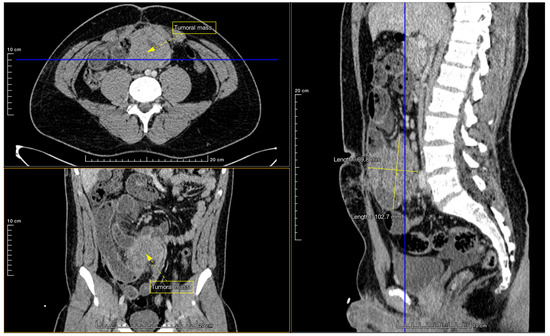

2. Case Report